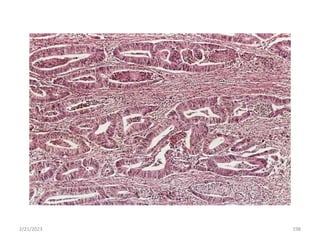

Adenocarcinoma: One with a glandular

growth pattern microscopically.

2/21/2023 218